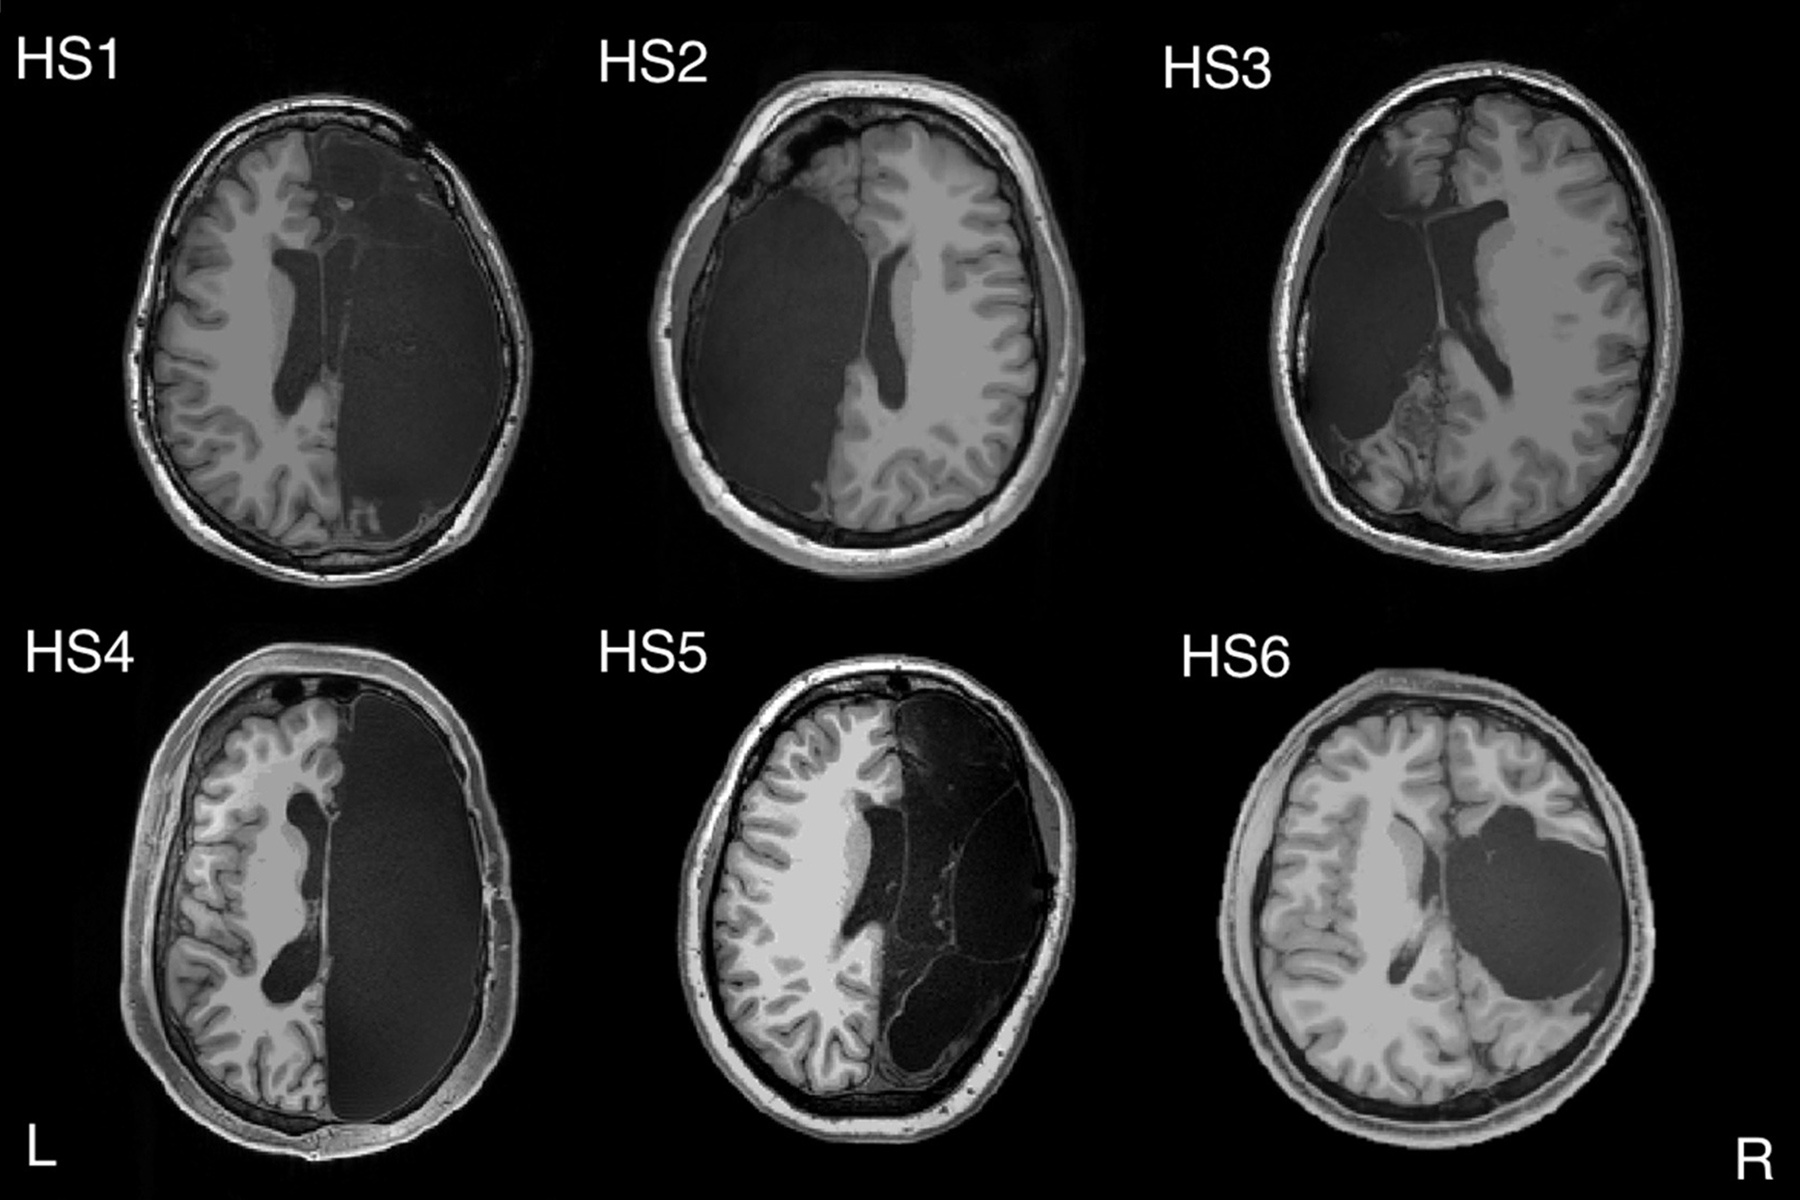

![]() |

| Phẫu thuật cắt bán cầu não được thực hiện tốt nhất với bệnh nhân ở độ tuổi rất nhỏ. Ảnh: Newsweeks. |

“Khi nhìn vào hình ảnh bản quét não của họ, chúng tôi đều nghĩ bộ não này thực sự không thể hoạt động được", Ralph Adolphs - nhà thần kinh học nhận thức tại Viện Công nghệ California và đồng tác giả của nghiên cứu - cho biết.